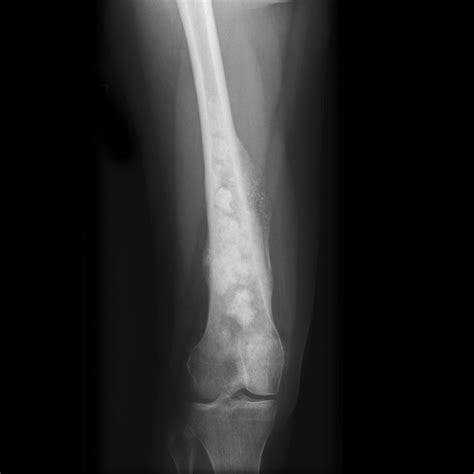

Common radiographic findings that might trigger a suspicion of osteosarcoma include:

• Cortical Destruction: A lack of well-defined borders indicating the tumor is aggressively breaking through the bone shell.

• Sunburst Pattern: Radiating spicules of bone formation that extend outward from the tumor into the soft tissue.

• Codman’s Triangle: A triangular formation of new bone that occurs when the tumor grows faster than the periosteum (the outer covering of the bone) can form new bone, resulting in an elevation of the periosteum.

• Soft Tissue Mass: Shadows outside the bone that suggest the tumor has breached the cortical bone and is invading the surrounding soft tissues.

Interpreting an Osteosarcoma X Ray requires a nuanced eye. Osteosarcoma is heterogeneous, meaning it can present in several different ways depending on its subtype and location. The appearance of the lesion often depends on whether it is predominantly osteoblastic (bone-forming) or osteolytic (bone-destroying).

Lesion Location Metaphysis of long bones (near the knee) Variable, often diaphyseal or epiphysis